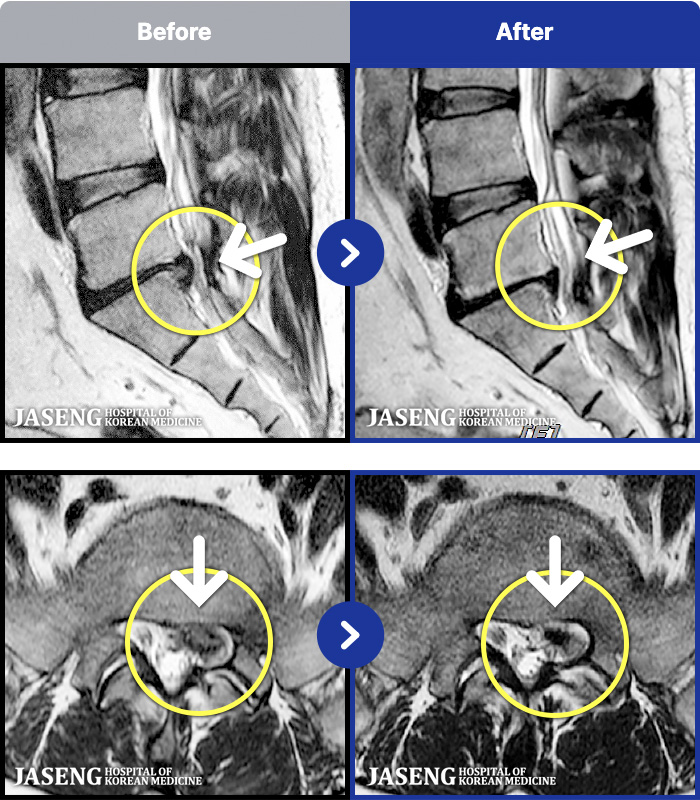

MRI ġ

1,237 MRI ũ ʸ Ȯϼ.